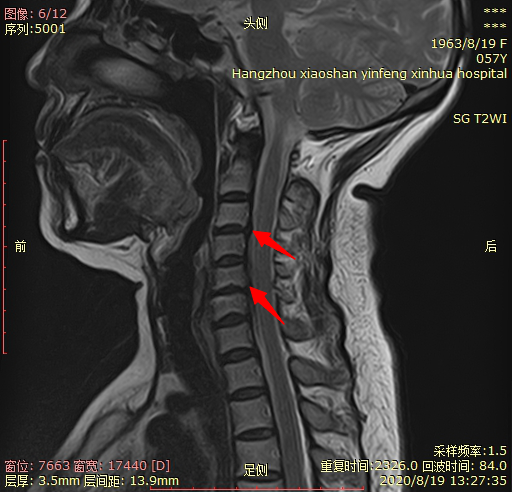

02 颈椎间盘突出。